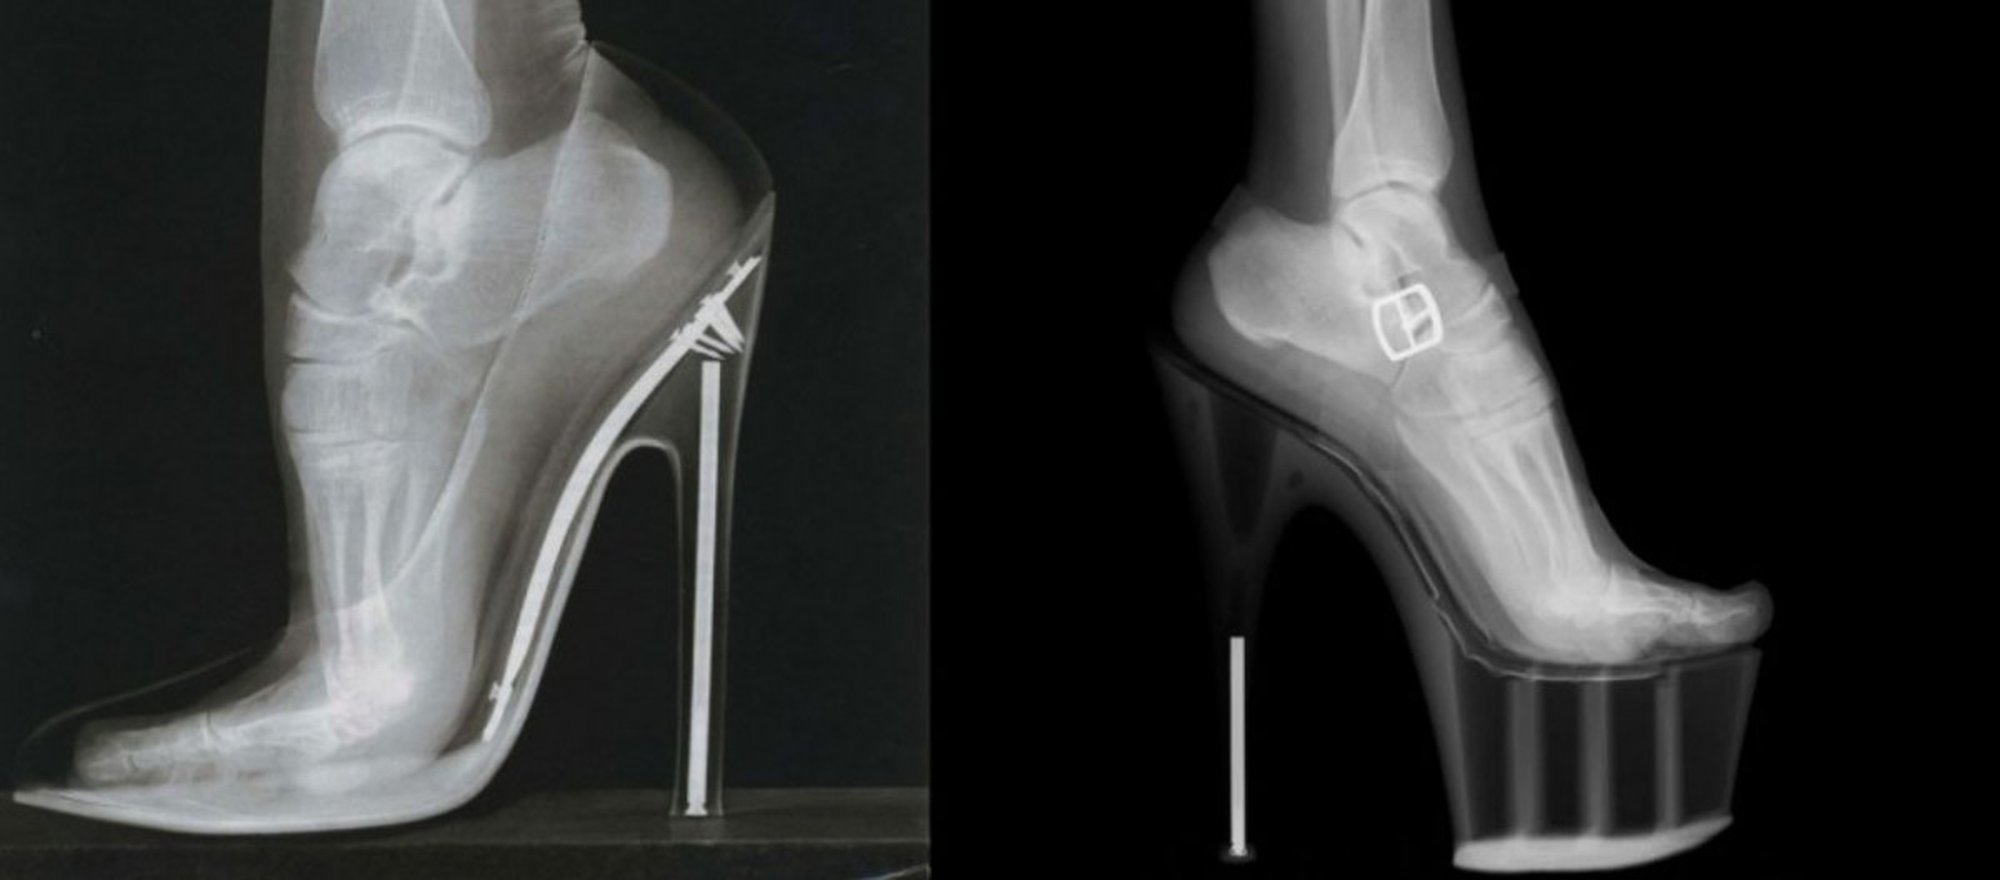

- Aşırı yüksek topuklu ayakkabıların uzun süreli kullanımı, ayaktaki Lisfranc eklemi çevresinde kemik aşınması ve kırıklara neden olan Lisfranc Kırılması veya Çıkığına sebep olabilir.

Dişilerin aşırı yüksek topuklu ayakkabıları uzatılmış süreler boyunca giymeleri sonucu oluşan kemik aşınması ve kırılmalarına Lisfranc Kırılması veya Lisfranc Çıkığı adı veriliyor. Lisfranc, çıkık ya da kırığın genellikle görüldüğü ayak eklemlerine verilen isimdir. Bu eklem, 9 kemiğin birbirine sıkıca bağlandığı bir bağ dokusudur.